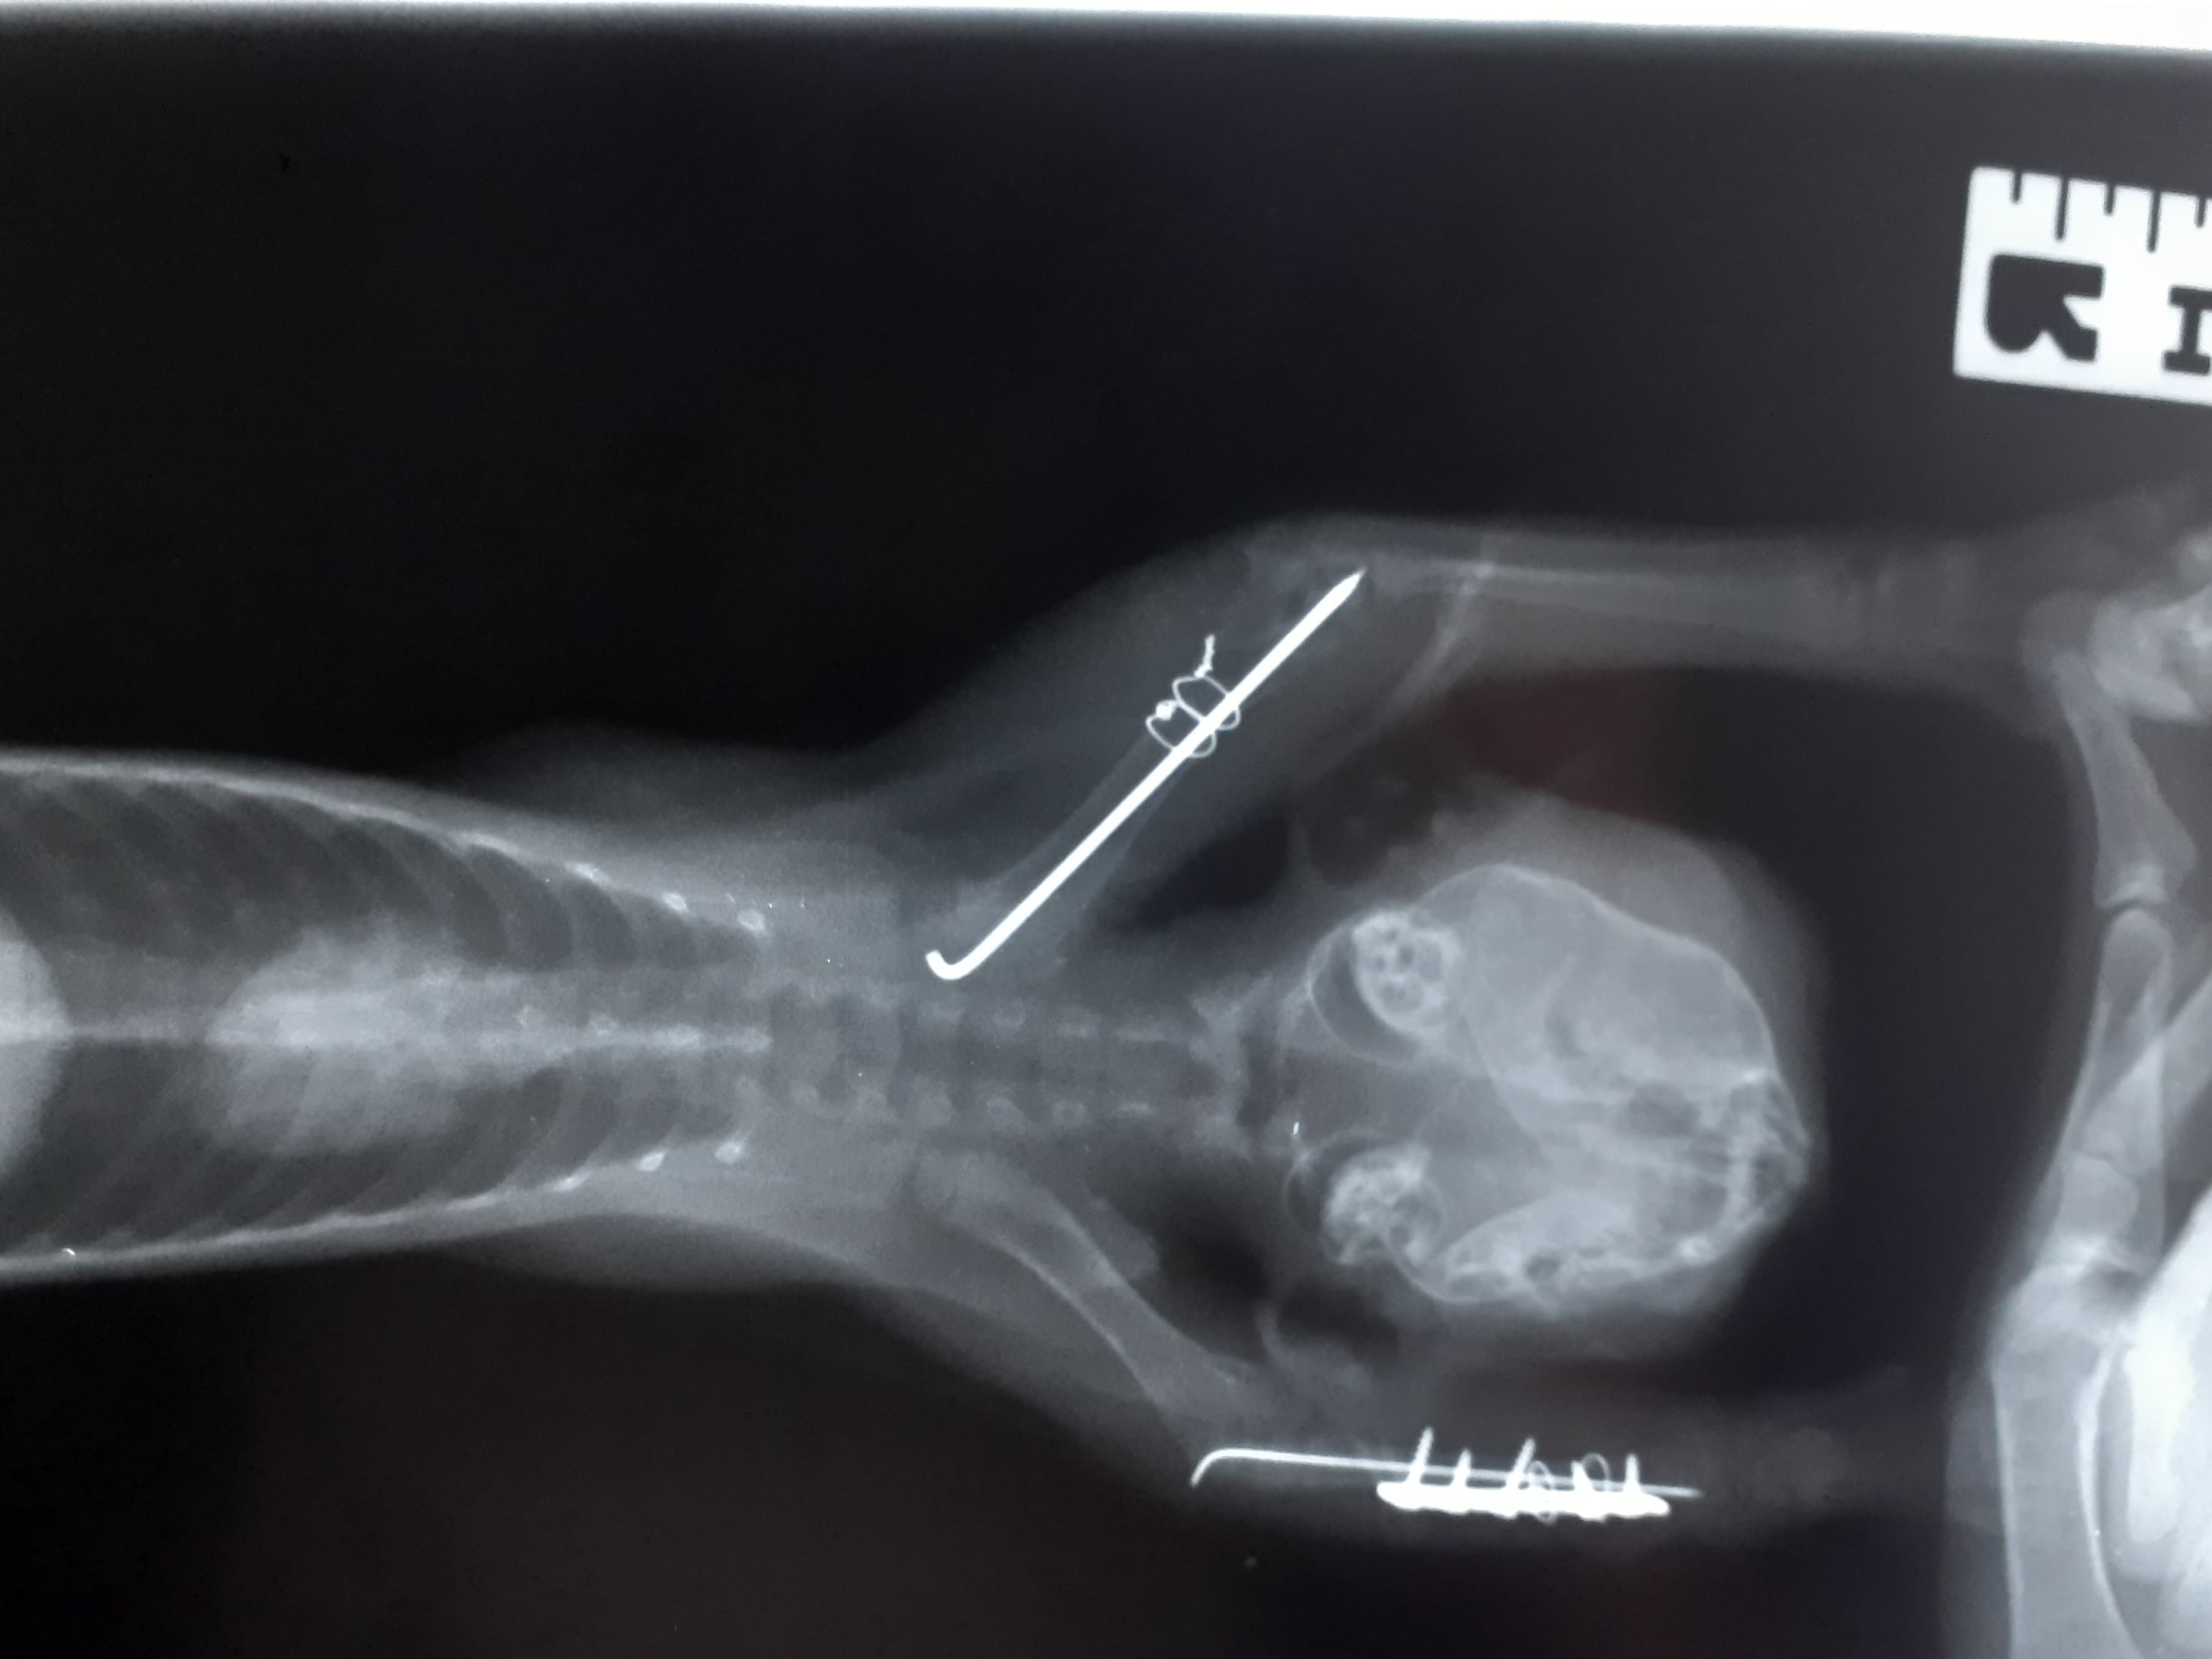

Právě jsme přijali zubožené koťátko v kritickém stavu. 😰 Koťátko je po srážce s autem, má zlomené obě přední nohy a problémy s očičkem, za kterým podle pana veterináře může stát zelený zákal. 😭 Lidé, kteří nás o koťátku informovali, ho nechali takhle ležet ve slámě, přestože drobeček musel mít neuvěřitelné bolesti a nedokázal se postavit. Muselo to pro něj být šílené. 😔

Koťátko jsme vyzvedli a vzali ho na místní veterinu, kde dostalo injekci na bolest a pan doktor ho prohlédl a ošetřil mu očičko. Následně jsme ho převezli k našemu panu veterináři, u kerého koťátko podstoupilo operaci nožiček. Pan doktor nám také prozradil, že jde o holčičku, dostala jméno Alex.

Zubožené koťátko, které jsme včera přijali, má jméno! Je to holčička a jmenuje se Alex. 🐱 Koťátko je hospitalizované na veterině, dostalo kapačky a už má za sebou operaci zlomených nožiček. Ty se zpevnily drátem a zafixovaly. Teď Alex čeká klidový režim a hojení, vyhráno ještě ale nemá - stále zde existuje riziko infekce. 😔 Moc doufáme, že k ničemu takovému nedojde a od teď už vše půjde dobře, to ale ukáže teprve čas. 🙏 Pokud jde o nemocné očičko, pan doktor se domnívá, že půjde o zelený zákal, ještě to ale nedovede říct jistě.